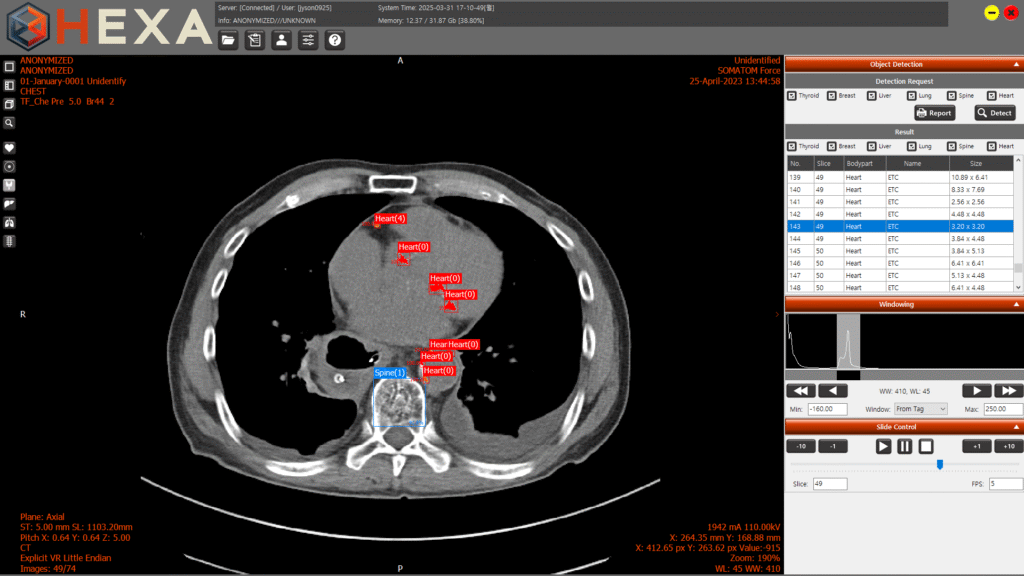

‘HEXA’는 한 번의 흉부 CT 촬영으로 갑상선·심장·폐·간·유방·척추 등 6개 장기의 이상 의심 영역을 AI가 자동으로 식별해 표시하는 솔루션이다. 주된 질환 판독 과정에서 간과될 수 있는 타 장기의 이상 소견을 포착하여 진단 누락 가능성을 줄이는 데 중점을 뒀다.

주요 기능으로는 CT 영상 수신 즉시 분석을 수행하는 ‘오토런(AutoRun)’ 기반 워크플로우가 적용됐다. 또한 구체적인 병명을 제시하는 대신 의심 부위를 시각적으로만 표시하여 임상의의 독자적 판단을 보조하는 UI를 채택했다.

엑스큐브는 서울바이오허브의 지원을 받아 의료기관과 공동 연구개발(R&BD)을 수행하며 알고리즘 검증 및 판독 효율성을 높였다. 현재 기본 뷰어 기능을 갖춘 1등급 의료기기 ‘HEXA:BASE’는 한국산업기술시험원(KTL) 시험에서 약 96%의 정확도를 기록했으며, 10여 개 의료기관에서 사용 중이다. AI 자동 검출 기능이 포함된 ‘HEXA Pro’는 2등급 인허가를 위한 기술 고도화 단계에 있다.